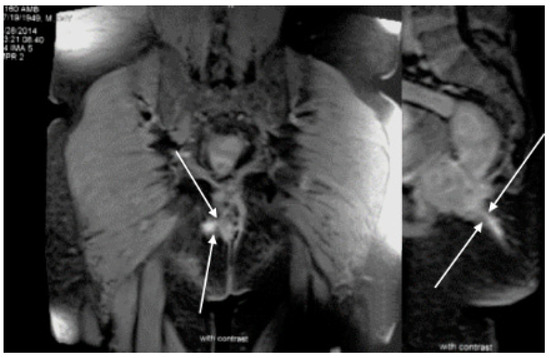

Case Report

Rectal Polyposis in Mucosal Prolapse Syndrome

by Yin Ping Wong, Connie Kabincong, Mohd Faisal Jabar and Geok Chin Tan

Diagnostics 2022, 12(4), 966; https://doi.org/10.3390/diagnostics12040966 - 12 Apr 2022

Abstract

Mucosal prolapse syndrome is also known as solitary rectal ulcer syndrome. It may either presents as an ulcer or polyp, which could mimic other pathological lesions such as juvenile polyp, hyperplastic polyp, adenomatous polyp, polyp related inflammatory bowel disease and adenocarcinoma. It can [...] Read more.

Mucosal prolapse syndrome is also known as solitary rectal ulcer syndrome. It may either presents as an ulcer or polyp, which could mimic other pathological lesions such as juvenile polyp, hyperplastic polyp, adenomatous polyp, polyp related inflammatory bowel disease and adenocarcinoma. It can pose as a diagnostic challenge to both the surgeons and pathologists due to the overlapping gross and histological features. The characteristic histological features of mucosal prolapse syndrome are fibromuscular obliteration of lamina propria and splayed hypertrophic muscularis mucosae. It can occur in a wide range of ages, including children and teenagers. Rectal bleeding is one of the common presenting symptoms. Here, we described two cases of mucosal prolapse syndrome presented as rectal polyposis and provide a discussion on its histological differential diagnosis. Full article